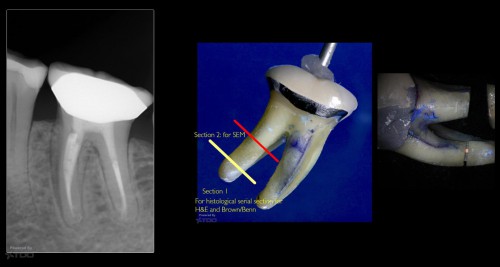

Had many emails on how to interpret some of the sections from our “fracture case” […]

How to detect a biofilm

By Gary Carr / February 27, 2019